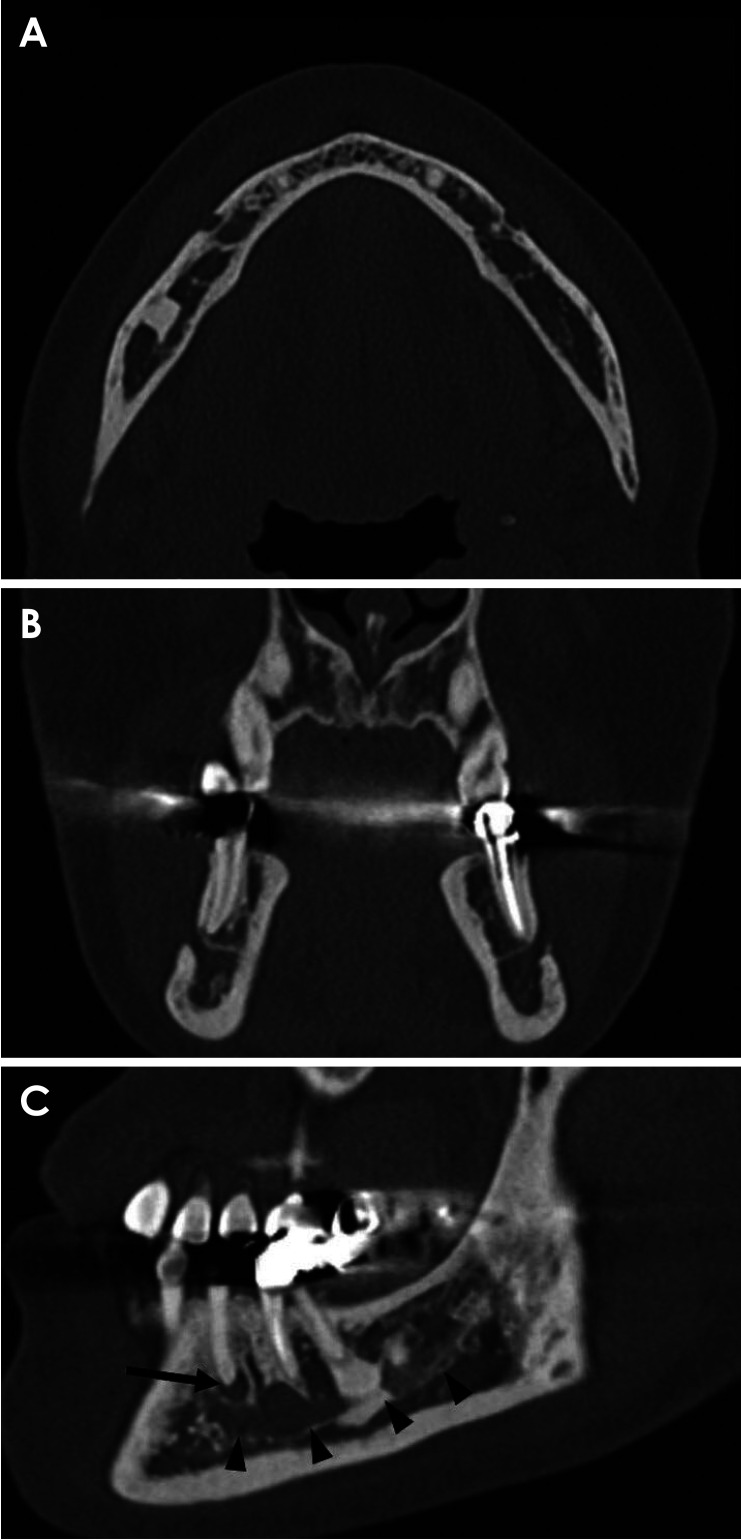

Components derived from an infected lesion within the bone can spread through various passages in the mandible, particularly via the mental foramen. Radiologically, the spread of infection is typically nonspecific and challenging to characterize; however, multislice computed tomography (MSCT) can effectively detect pathological changes in soft tissues and the bone marrow space. This report describes the case of a 55-year-old woman who experienced mental nerve paresthesia due to a periapical infection of the right mandibular second premolar. MSCT imaging revealed increased attenuation around the periapical lesion extending into the mandibular canal and loss of the juxtamental foraminal fat pad. Following endodontic treatment of the tooth suspected to be the source of the infection, the patient's symptoms resolved, and the previous MSCT imaging findings were no longer present. Increased bone marrow attenuation and obliteration of the fat plane in the buccal aspect of the mental foramen may serve as radiologic indicators of inflammation spreading from the bone marrow space.